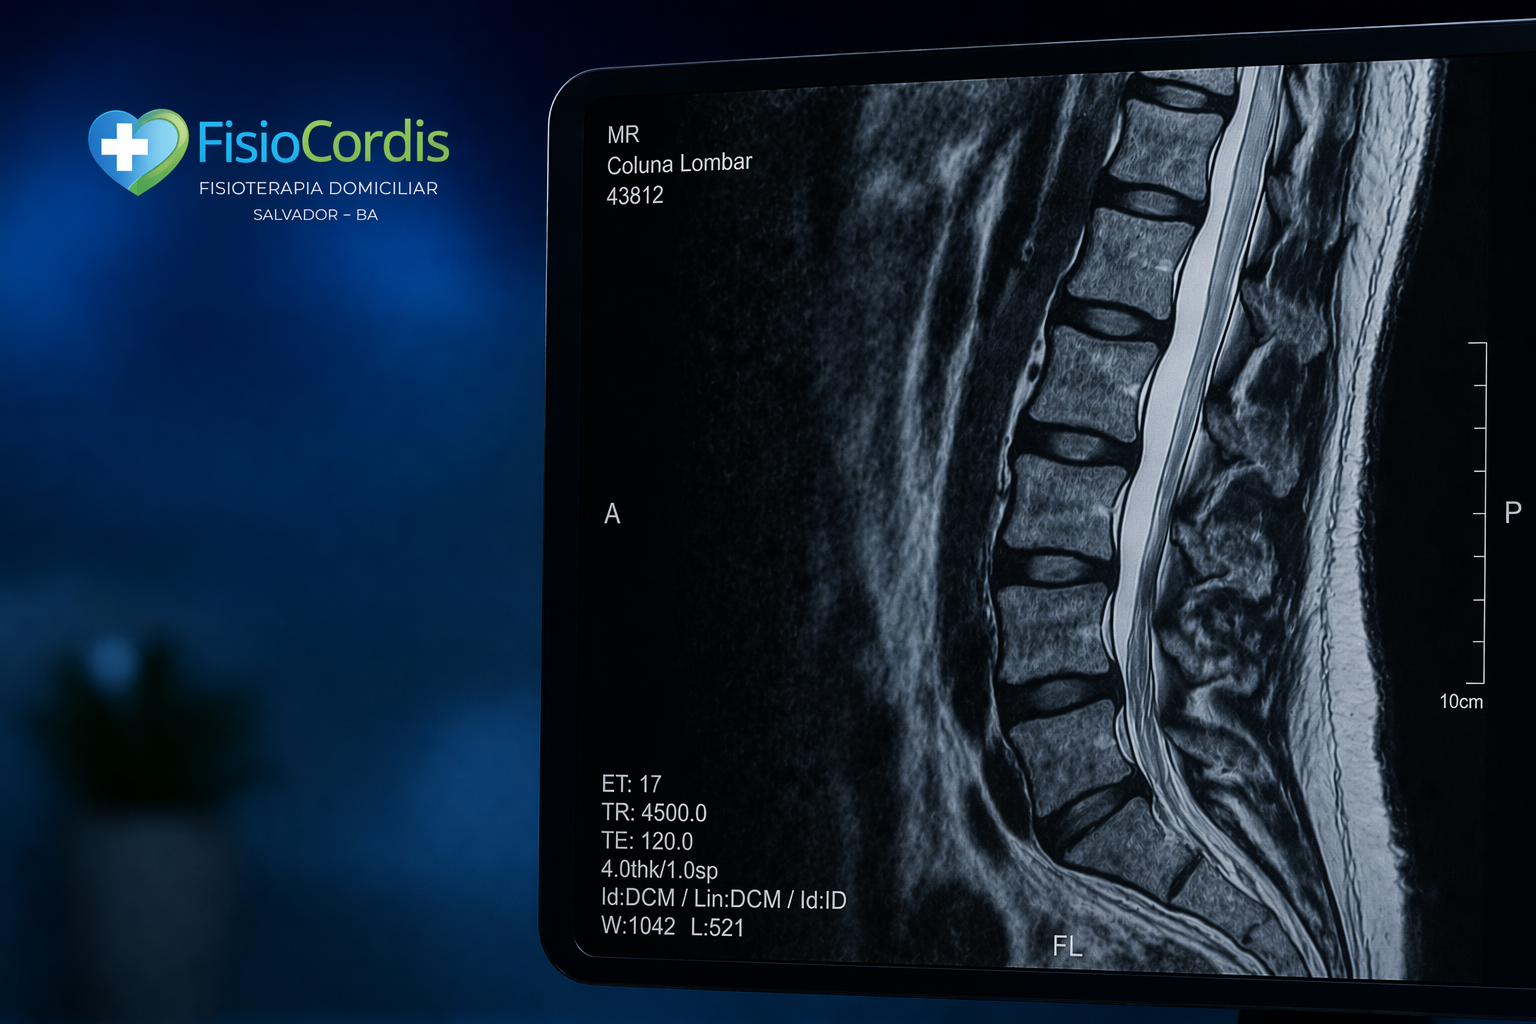

Além disso, exames como a ressonância magnética ajudam a identificar alterações na coluna, como hérnia de disco, degeneração e compressões nervosas. Dessa forma, é possível direcionar o tratamento de maneira mais precisa e segura.